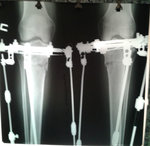

Рентген контроль в 1,5 месяца с момента снятия аппаратов.

Всё в норме! Разрешено все нагрузки без ограничения, каблуки любых размеров! Фото на каблуках за Вами!